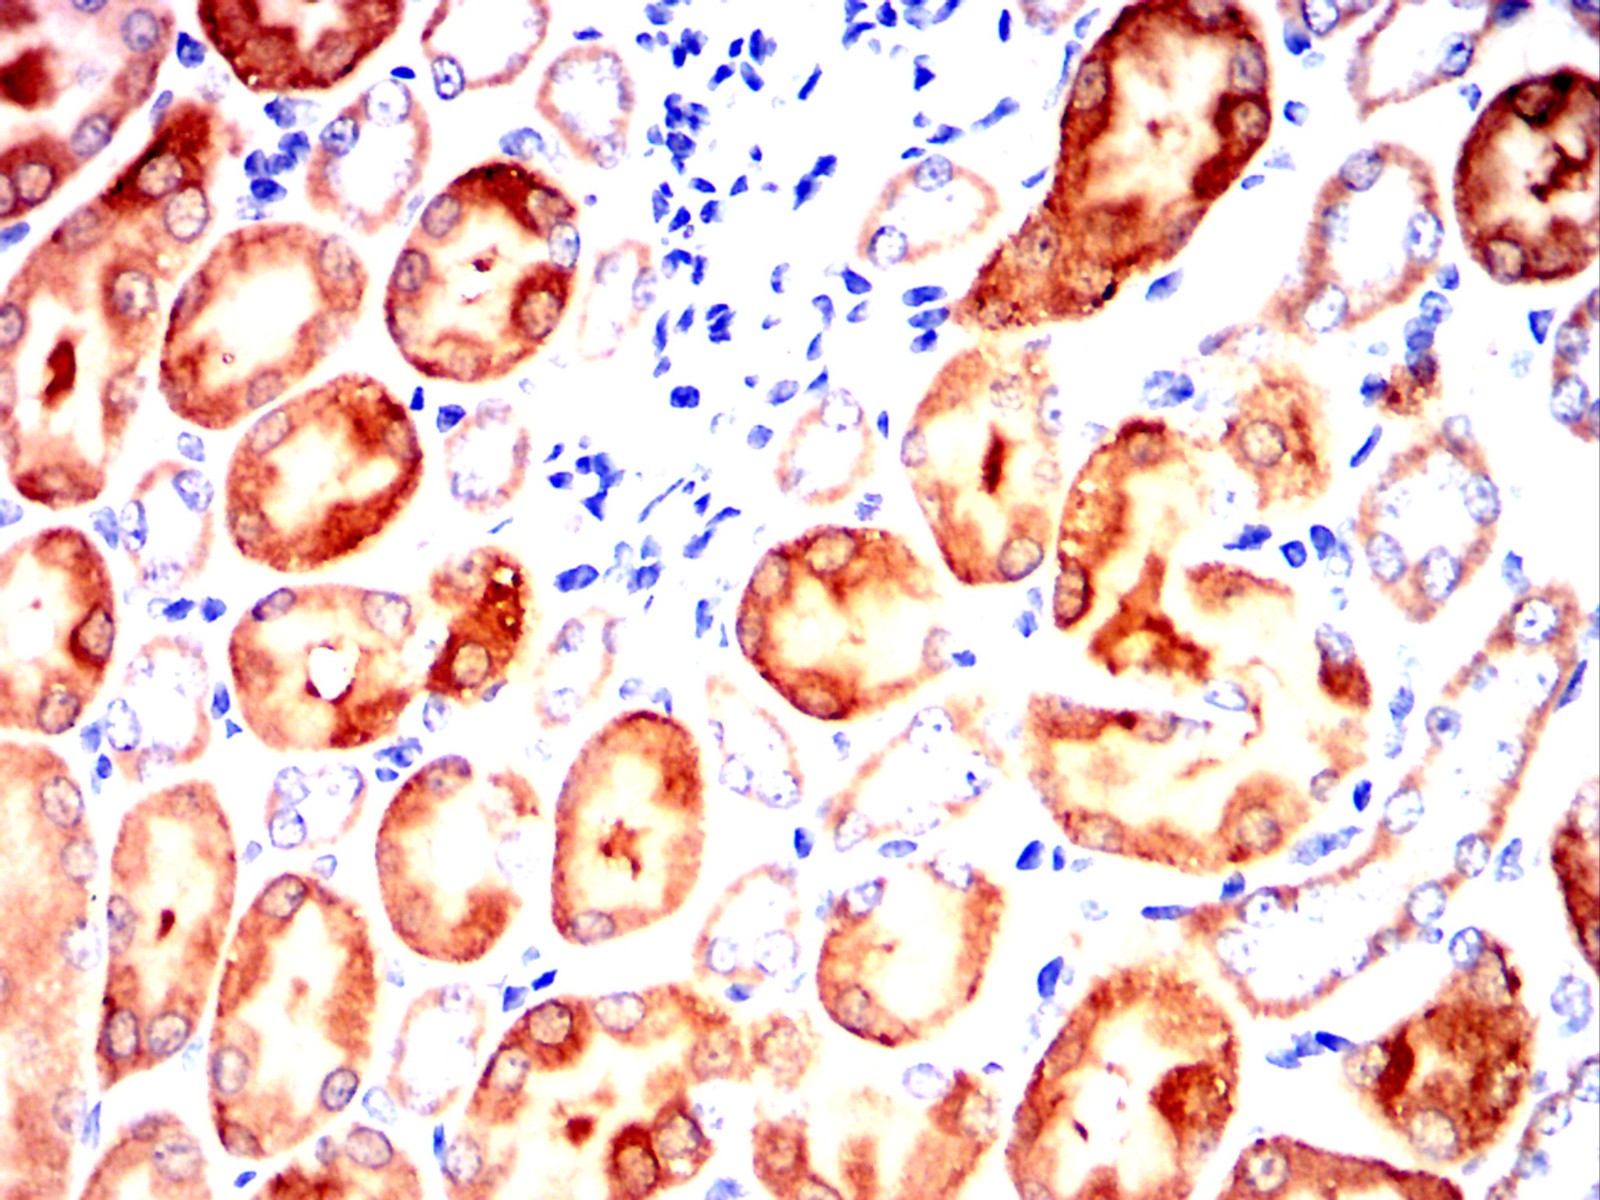

Immunohistochemical analysis of paraffin-embedded human lung cancer tissues using CCL15 mouse mAb with DAB staining

Immunohistochemical analysis of paraffin-embedded Rat kidney using CCL15 mouse mAb with DAB staining